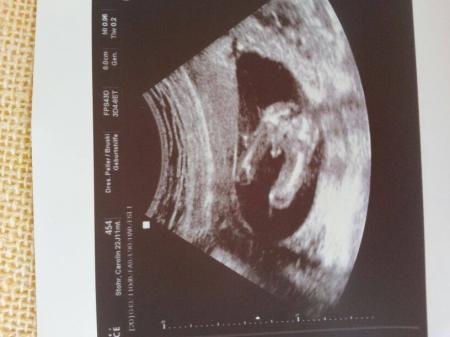

Ganz ehrlich? Das ist ein wirklich bescheidenes bild... Der ist echt gemein.. gibt es hier nicht ein experten forum? Frag da mal Ich schätze ein Mädchen aber nur weil das outing bild von mir ein junge ganz anders aussah, zeige ich dir mal Lg

Bild zu

Ich würde sagen Junge. Sah bei meinem Jungen vor drei Jahren fast genau so aus!!! GLG